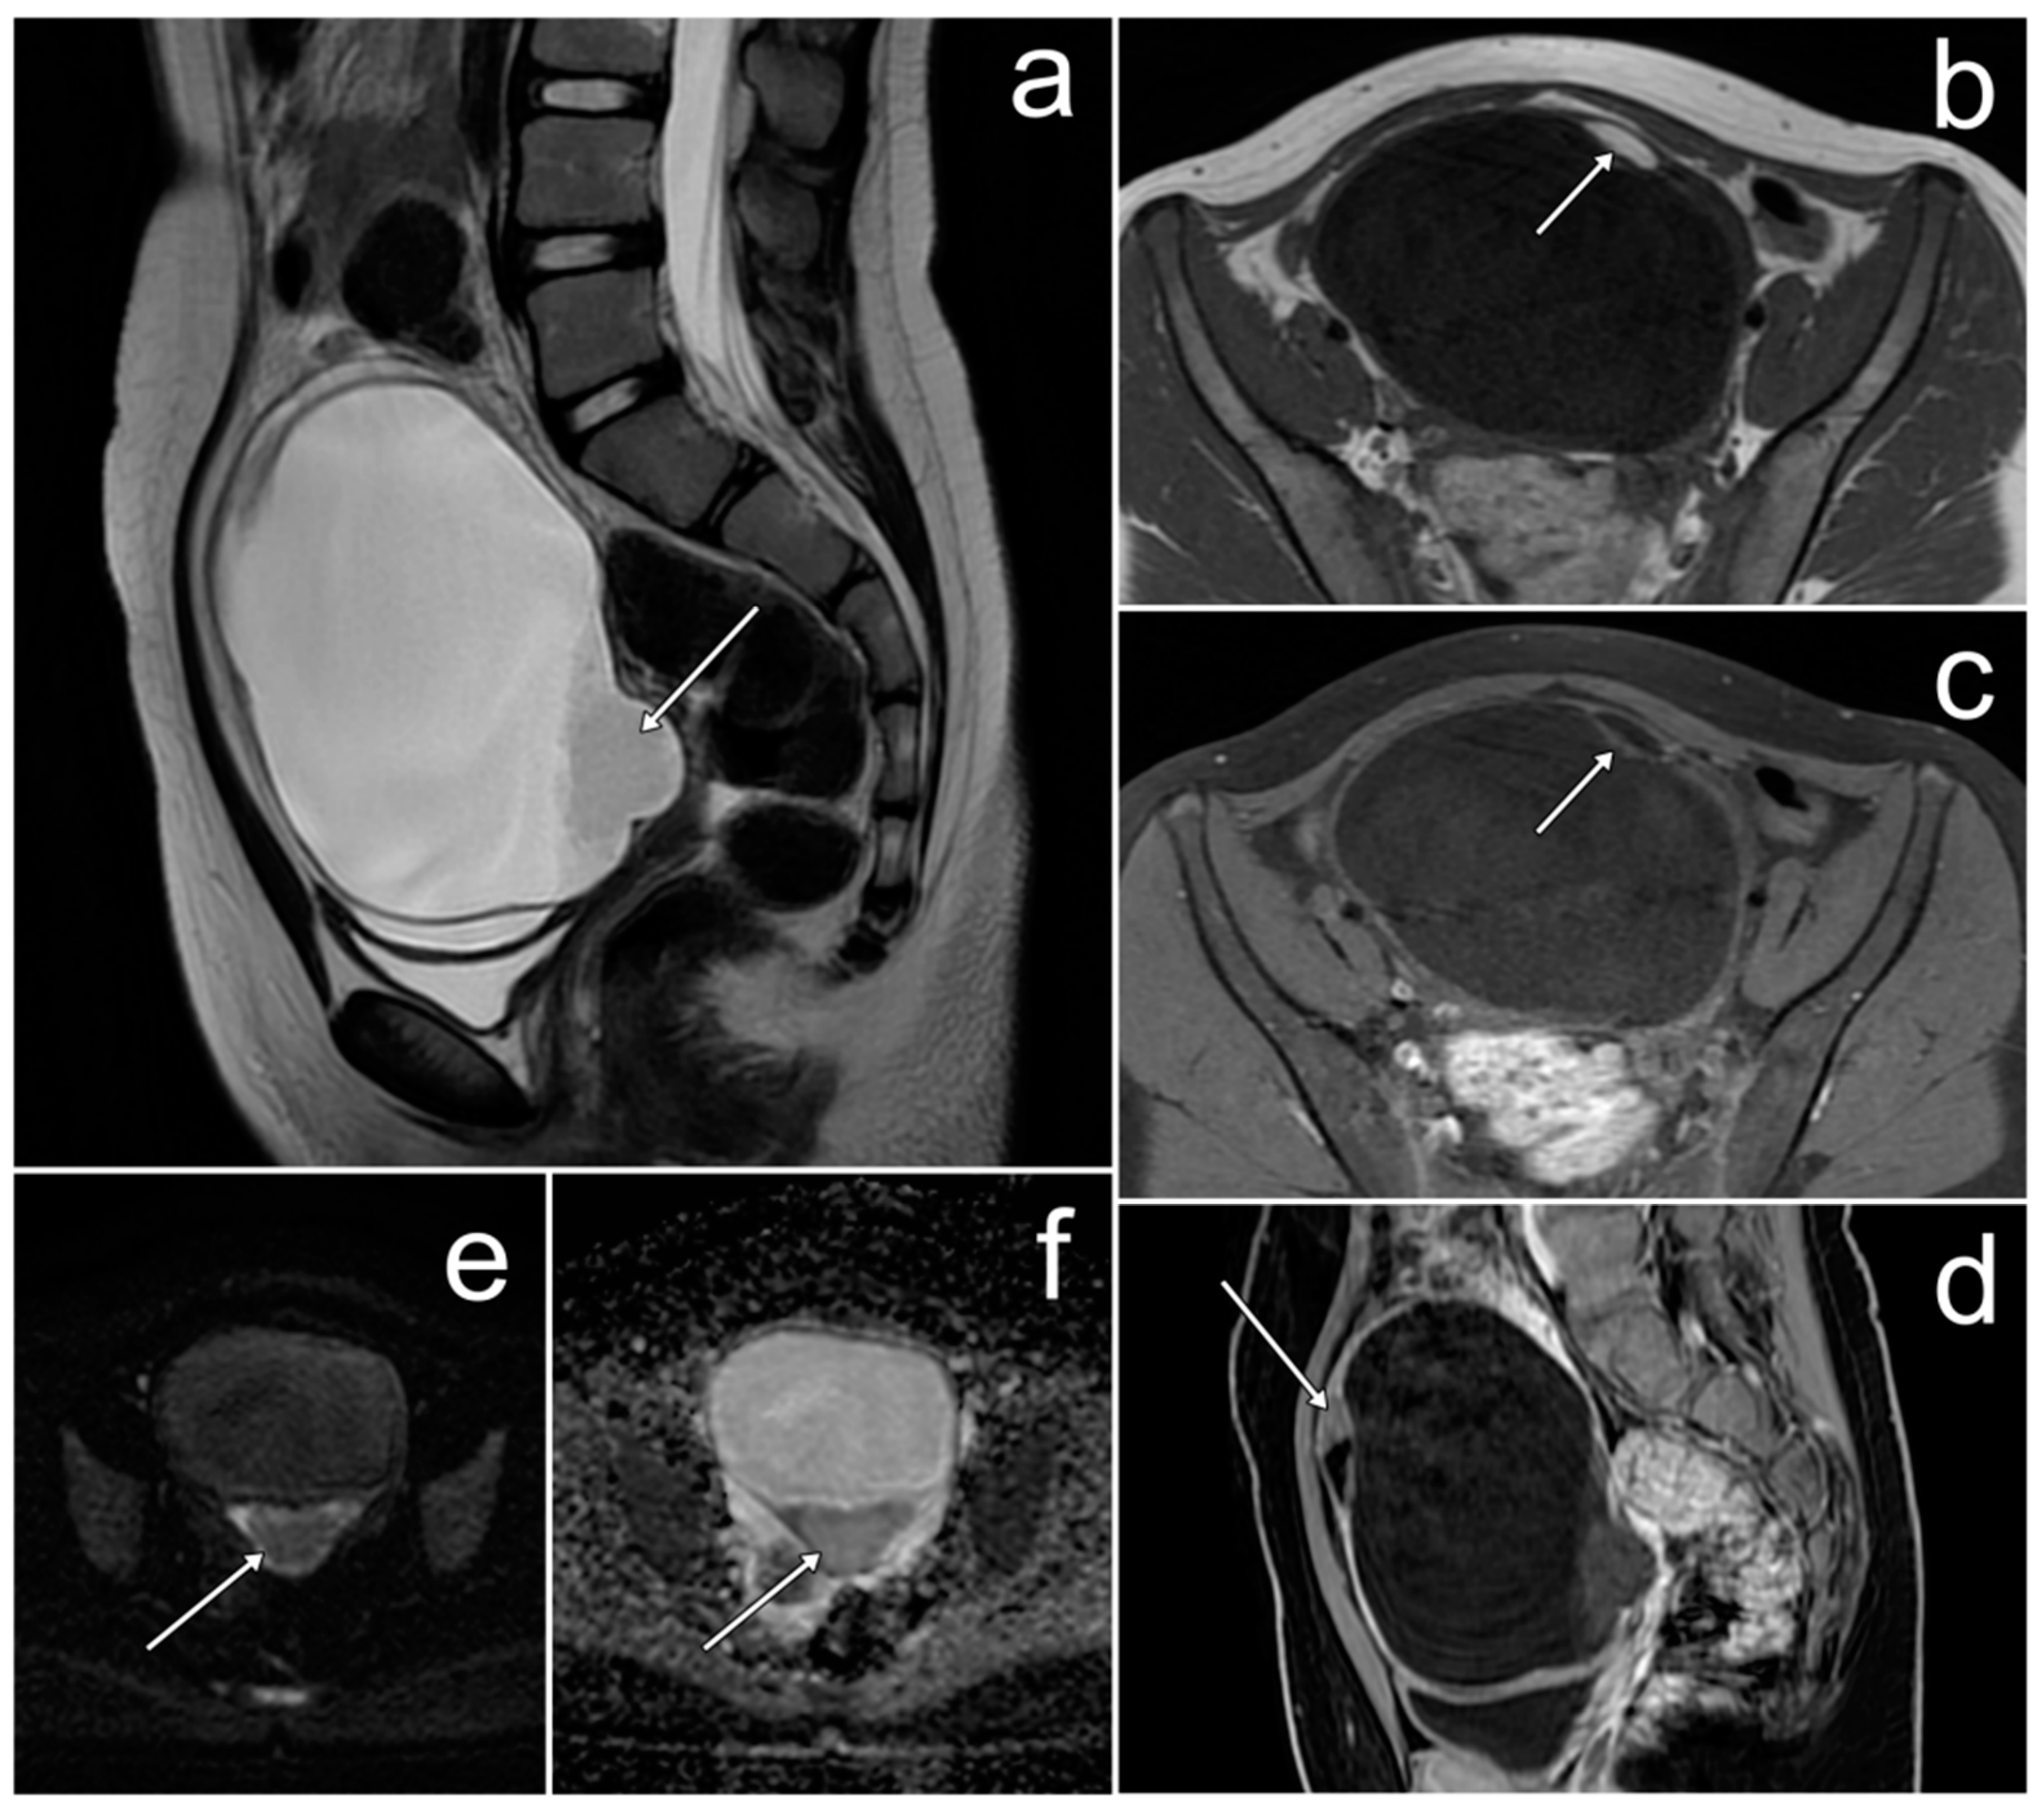

3.2. Ewing Sarcoma/Primitive Neuroectodermal Tumor of the Ovary

Case Report

| Ewing sarcoma/primitive neuroectodermal tumor of the ovary | variable; three MRI patterns: (1) large, solid, heterogeneous tumor with restriction diffusion and varying degrees of contrast enhancement, (2) mass consisting of thick-walled cystic lesions with numerous septa, (3) combination of (1) and (2) | - | non-specific; abdominal/pelvic pain, mass in the abdomen/pelvis, weight loss, bloating, irregular periods, abnormal vaginal bleeding, back and lower limb pain |